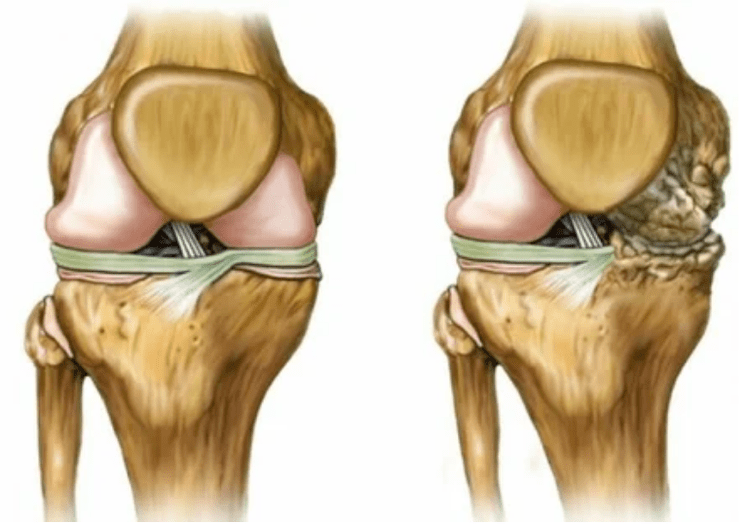

- Reducing the gap in the gap of the joint, which becomes noticeable in the photo.The stage of the violation is determined by the diagnostic tantegenologist.The patient feels the complexity or inability to fully straighten and bend the limb;

- Deformation of the joint, cartilage takes on an irregular shape, provoking curvature;

- worsening in the patient's condition with complete destruction of the joint.

- Stage 2. Due to the supply deficit, the necessary cartridges are destroyed, bone growths are formed on the surface of the cartilage.The pain is more pronounced, increased after a long break, is eliminated by little physical labor.The pain is accompanied by inflammation.The muscles are stretched, leading to weak or medium -impaired motor functions.

- 3 degrees.Often there is pain, it is difficult to move the limb due to changes in the joint.The lesions are extensive, becoming noticeable for the naked appearance.There is a deformation in the joint place, the affected area swells and becomes red.The axis of the limbs is disturbed, leading to the complexity of the movement.Pathological changes cause shortening.Shrubs and contractures appear.The adjacent muscles are shortened or stretched, from which the contractile function is weakened.